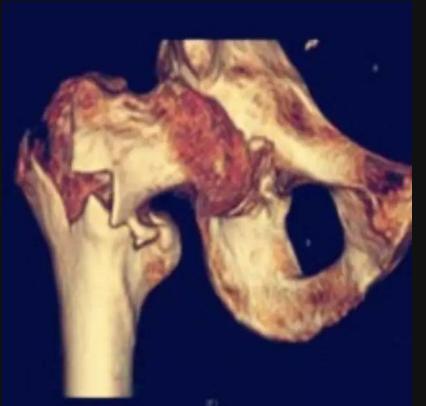

C:髓内钉固定

就是在骨髓内打入固定用的钉棒。由于这个部位的骨折往往都是高龄患者,带有严重的骨质疏松,一摔往往都是粉碎性的,破镜很难重圆,因此通过这种插入髓腔的髓内钉技术,就像穿糖葫芦一样,给断掉的骨头一个主心骨。让骨头自己愈合。

同时呢这个手术是一种微创技术,只需要开2-3个很小的切口就可以完成。做的熟练的骨科医生,从切口到完成手术只需要20分钟。